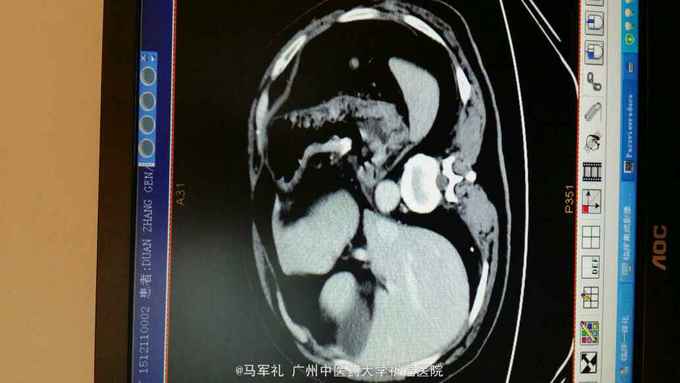

体检:T:36.3 ℃ P 95次/分 R:22 次/分 BP 115/78 mmHg 皮肤、巩膜无黄染,贫血貌,心、肺听诊无异常。腹部较平坦,未见胃肠型及胃肠蠕动波,无腹壁静脉怒张,腹式呼吸活动不受限,腹肌柔软,全腹无压痛及反跳痛,肝区无压痛,肝浊音界位置正常,肝脾未触及,Murphy征(-),移动性浊音(-),双肾区无压痛及叩痛,肠鸣音正常,未闻及血管杂音。 辅助检查:1.肿瘤标记物:CEA、AFP、CA153、CA199、TPSA均在正常范围。 2.胃镜+病理:胃底菜花样肿物,4cm×4cm,质硬。病理:中分化腺癌,HP(-)。 3.CT:胃底近贲门处局部组织不规则增厚。肝S2段小血管瘤,双肾多发小囊肿,胆、胰、脾未见异常;右肺多发泡性肺气肿。

诊断:胃癌 治疗:入院后行常规术前检查,术前准备完善后在气管内插管全麻下行腹腔镜下(全胃切除)胃癌根治术,术中探查肝脏及腹腔其它部位未见明显肿瘤转移。肿瘤位于胃底近贲门处,镜下观察未侵出浆膜,与周围组织器官无侵犯及粘连。腔镜下行全胃切除、胃癌根治术,于腔镜下行食道-空肠Roux-en-Y吻合术。手术顺利,术后恢复好,术后第4天肛门恢复排气,术后第5天恢复排便,术后第6天口服碘剂造影证实无吻合口漏,遂拔除胃管,逐渐恢复饮食,术后10天出院。术后病理报告:胃底中分化腺癌,溃疡型,大小4cm×3cm×2cm,侵润胃壁全层,侵犯食管壁。两切缘未见癌累及。食道下端吻合器切除之一圈组织未见癌,淋巴结见转移癌(胃小弯侧2/13,胃大弯侧0/2)。免疫组化:CK20(-),CK7(+),GST-π(++),Her-2(-),Ki-67(40%+),PgP(-),TOPOⅡ(++),villin(+),P53(80%+)。